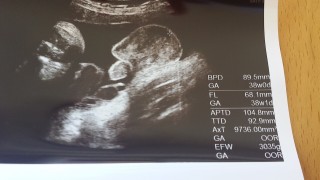

写真:37w2d:ケイトさん:2900g

3035グラムの男の子です。 エコー中あぐらをかいていました。 画像は、タマタマです。 胎動もしっかりあり、 なにかの骨をグリグリ押し付けられてて いつも右横腹が鋭く尖ります。 腰骨を押し広げられるような 痛みがあったり、いよいよかと楽しみです。 余計な食欲は、気合いで我慢しています(;_;)

推定体重2900gの元気な男の子です。 いつ産まれるかドキドキの毎日、 昨日の健診では、何だか悩んでるみたいだね、って先生に言われました(笑) 今までのエコーを見ると私の父に似てると思ってたけど、なんだか旦那にも似てる気がしてきました。